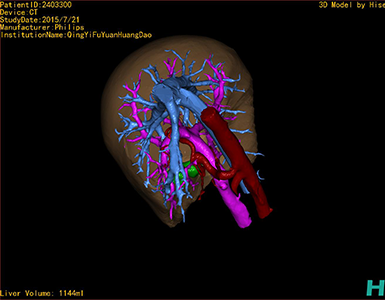

将0.625mm双源薄层CT资料的静脉期和动脉期Dicom格式文件导入海信CAS系统。

通过调节窗宽窗位调整CT序号,对肿瘤,肝实质,胆囊,下腔静脉,肿瘤,肝动脉、门静脉及肝静脉等进行三维重建;系统自动计算肿瘤体积和肝脏体积。

模拟手术操作,自动计算切除肿瘤体积。肝脏体积为1096ml,胰腺肿瘤体积为115.5ml,通过比对12-13岁正常肝脏体积为1116.86±158.78 ml,通过术前模拟手术,精准判断切除后肝脏体积无明显变化,避免肝衰竭发生。

术前三维重建:

重建图片